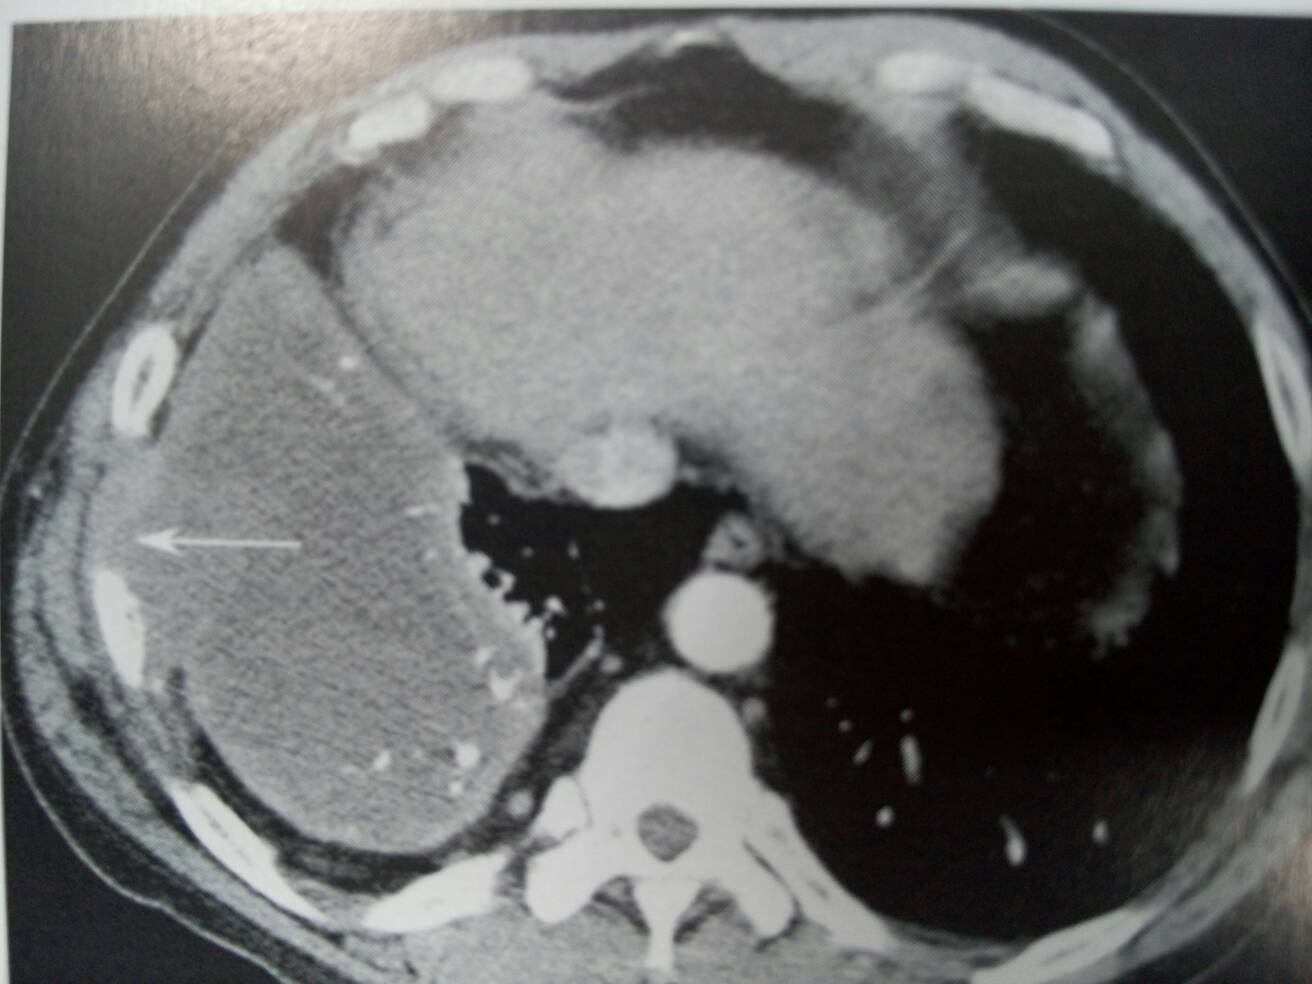

胸膜淋巴瘤。右侧胸腔积液,胸膜有结节样增厚,并有右侧胸壁侵犯及肋骨破坏。箭头所指。